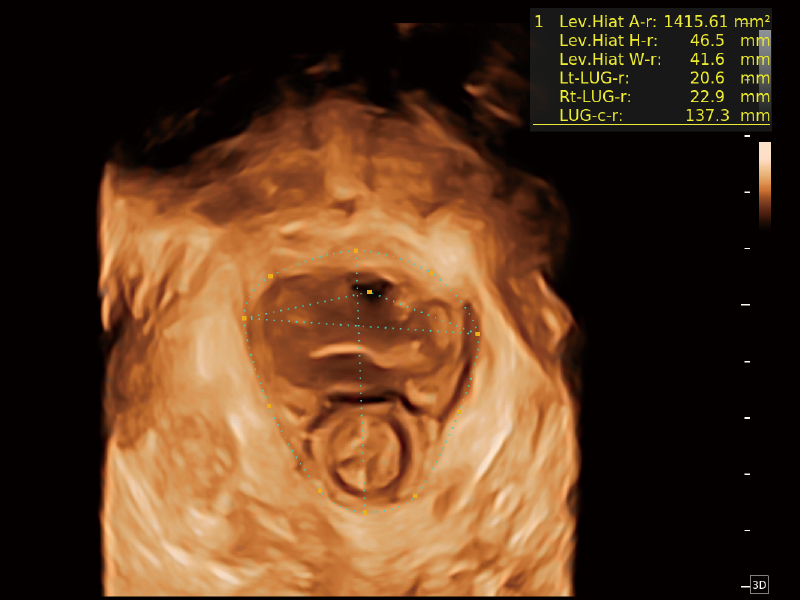

梦溪®P80以“关爱女性”为基石,提供全方位的解决方案,量身定制以满足女性的健康需求,涵盖妇科、生殖健康检查、产前筛查及产后康复等领域。